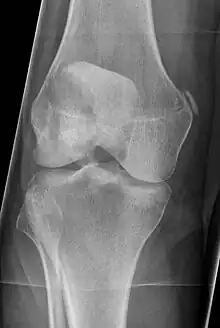

Pellegrini-Stieda syndrome. Also visible is a fracture of the patella.

Pellegrini–Stieda syndrome (also called Stieda disease and Köhler–Pellegrini–Stieda disease) refers to the ossification of the superior part of the medial collateral ligament of the knee. It is a common incidental finding on knee radiographs. It is named for the Italian surgeon A. Pellegrini (b. 1877) and the German surgeon A. Stieda (1869–1945).[1]